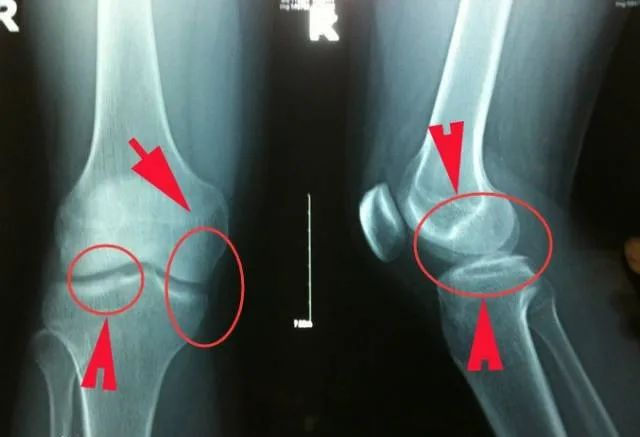

有网友就质疑,过多的体育锻炼会不会影响骨骼发育,孩子长不高!

骨骺板(生长板):骨骼板处于骨骼连接处的两端,随着年龄的增长,它们会不断硬化,适当的健身运动,可以促进骨骺的增生

真正会影响身高的不是健身,而是过度健身、不规范健身

而今井隆星的父亲之前也在社交账号上透露,没有过度训练自己的儿子,从不做负重训练腿部,只是做做徒手深蹲、跑跑步、踢踢腿~